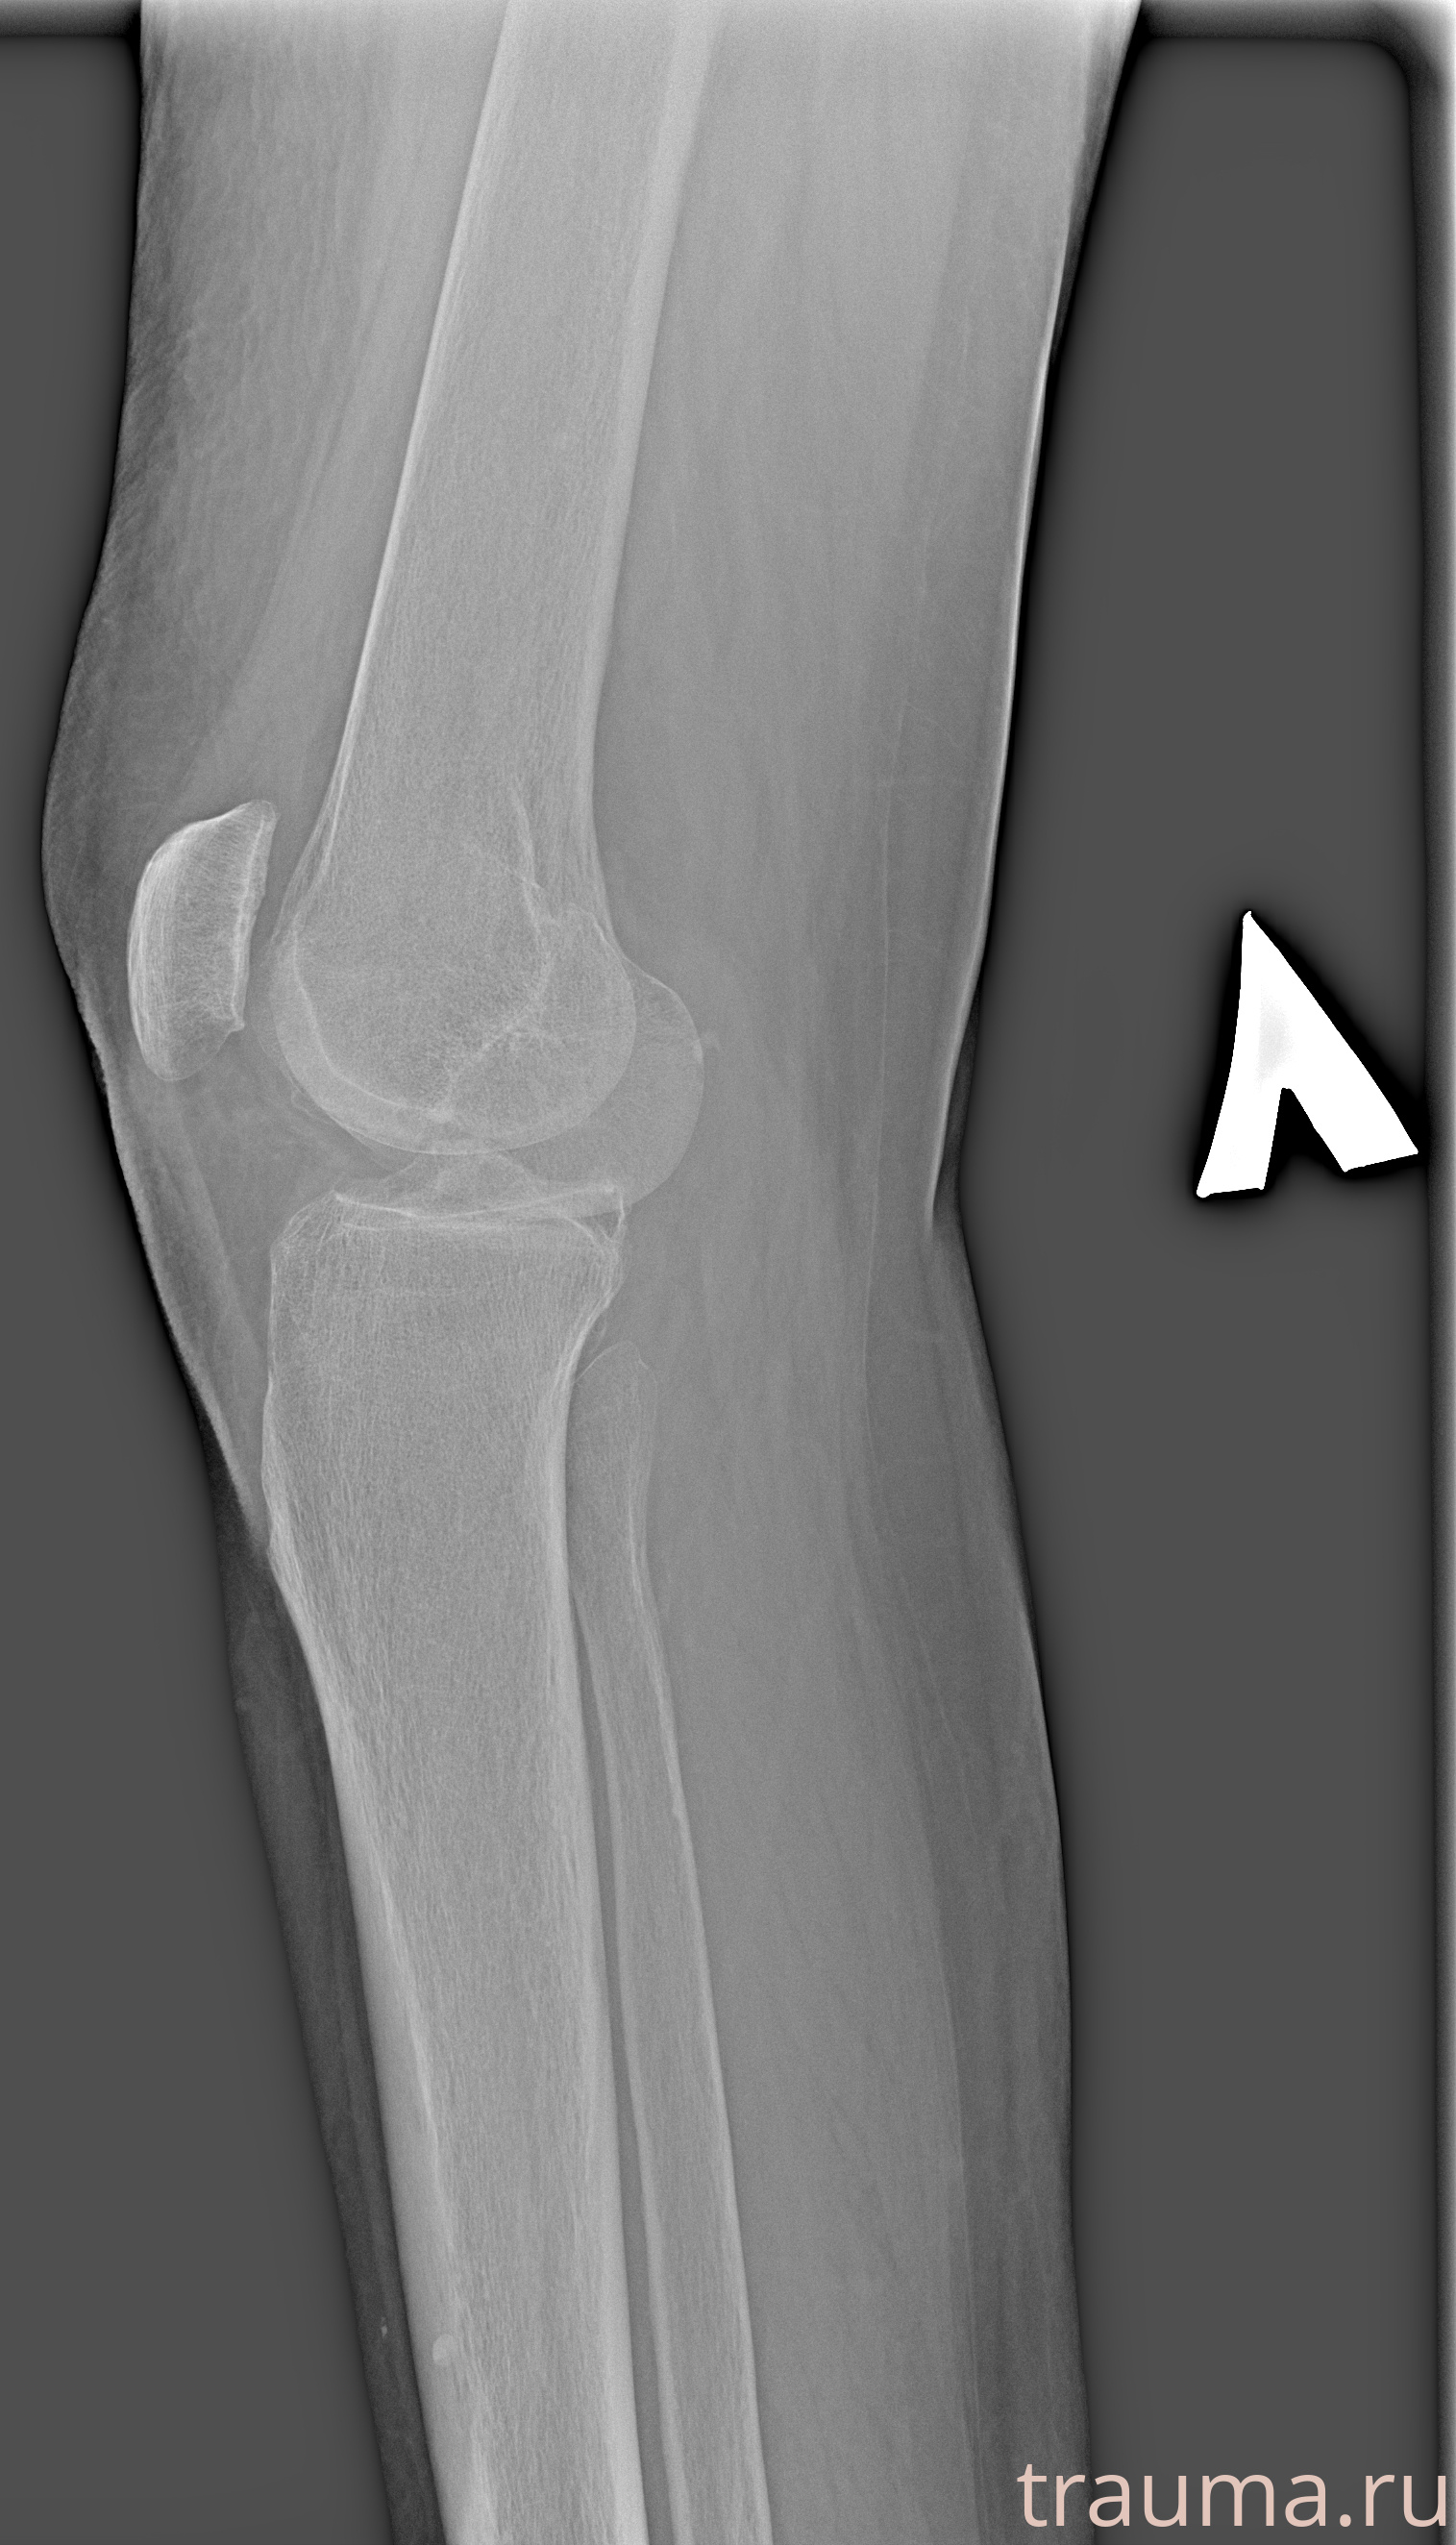

Рентген на дому: по вашему адресу приезжает врач-рентгенолог, травматолог-ортопед с мобильным рентгеновским аппаратом, проводит диагностику травмы или заболевания, делает необходимые рентгенограммы, дает рекомендации по дальнейшему лечению. Получить качественные снимки в домашних условиях возможно благодаря уникальной методике, разработанной МосРентген Центром для института  Склифосовского